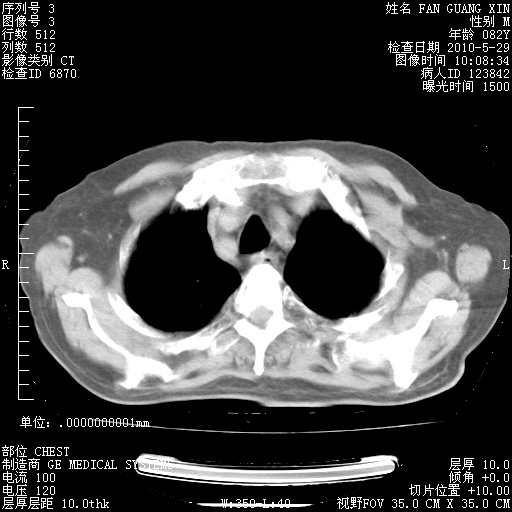

再治疗10天后的肺部CT

再治疗10天后的肺部CT 纵膈窗